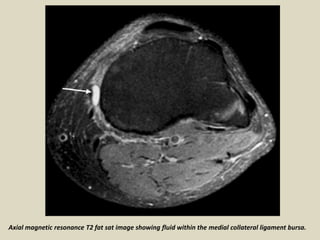

Medial Collateral Ligament Bursitis

The medial collateral ligament bursa is located between the superficial and deep layers of the

medial collateral ligament. Clinically, fluid collection in this bursa mimics a medial meniscus tear

and/or medial collateral ligament tear. On MRI, medial collateral ligament bursitis appears as a

T2 hyperintensity between the superficial and deep fibers of the medial collateral ligament. It

must be differentiated from meniscocapsular separation. In meniscocapsular separation, in

addition to fluid collection between the superficial and deep fibers of the medial collateral

ligament, there is a tear of the peripheral corner of the medial meniscus and meniscal

displacement from the outer cortical margin of the tibia.

Medial collateral ligament bursitis. A 54-year-old female presented with knee swelling: sagittal true inversion recovery

magnitude (TIRM) (A) and axial T2W (B) images show a distended medial collateral ligament burse (arrows)

Coronal magnetic resonance T2 fat sat image showing fluid within the medial collateral ligament bursa.

Medial collateral ligament bursitis located between the deep MCL

(yellow arrow) and the superficial MCL (green arrow).

Axial magnetic resonance T2 fat sat image showing fluid within the medial collateral ligament bursa.